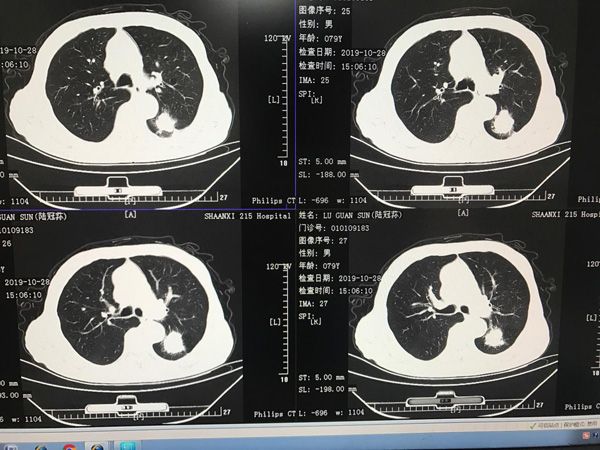

患者陆叔,已经79岁高龄,本月就该过80岁生日了,本该在家儿孙满堂,享受天伦之乐,可最近却愁容满面、心事重重,家里人也焦急万分。原来是陆叔在一月前体检时胸部CT发现左肺下叶长了一个肿瘤,辗转多家医院,却因为年龄太大、风险太大而否定了手术方案。家属经多方打听,怀着试一试的心情来到了陕西省核工业215医院胸外科门诊,薛锋主任接诊后,凭借他多年的临床经验,特别是在高龄患者手术方面的丰富经验,决定为陆叔手术治疗。

经过积极的术前准备后,于最近在薛锋主任主刀下,胸外科手术团队成功经电视胸腔镜微创下行根治性左肺下叶切除手术,由于解剖上肺动静脉走形复杂,变异多,血管壁薄易破,手术中稍不小心就会引起大出血,危及患者生命,导致手术失败,薛锋主任凭借高超的手术技巧和丰富的手术经验仔细解剖分离肺血管及支气管,成功切除了病灶。